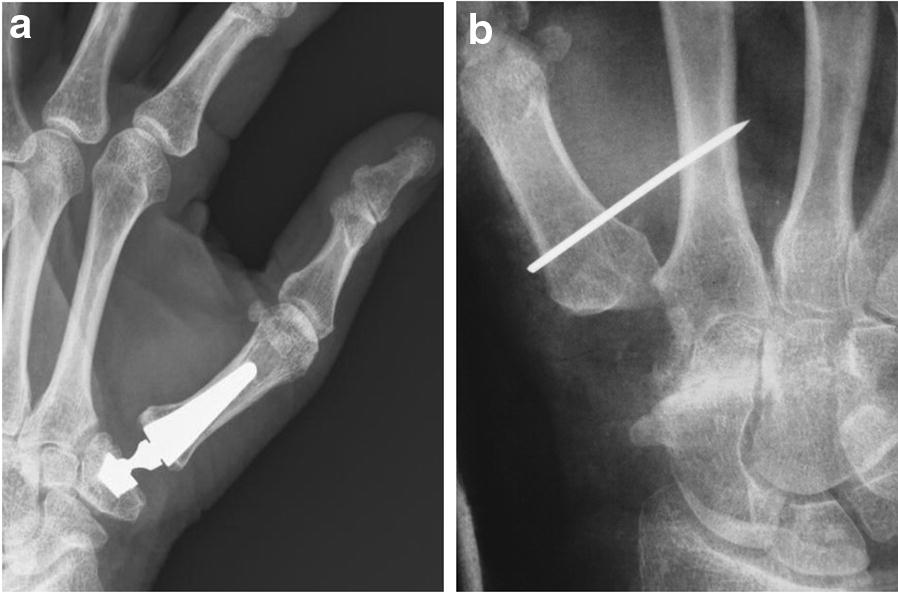

All surgical procedures were performed under plexus anesthesia and using a tourniquet by a senior hand surgeon assisted by a resident surgeon. For RA, we employed a technique that included restoration of the ligament connection between the first and second metacarpals after extirpation of the trapezium. We used a dorso-radial incision beginning at the base of the thumb centered over the trapeziometacarpal joint. Using blunt dissection, the radial nerve and artery and their branches were identified and protected. Then, using sharp dissection, the capsules of the trapeziometacarpal joint and the STT joint are identified and incised longitudinally. While paying attention to the radial artery, we extracted the trapezium. Furthermore, a distally based extensor carpi radialis longus (ECRL) tendon strip (4 cm) was used for suspension and ligament reconstruction by passing it through the base of the first metacarpal and fixing it under appropriate tension via a Micro Mitek bone anchor (Johnson and Johnson, USA). To allow for tendinous healing and maintenance of reduction, a temporal arthrodesis was placed with a Kirschner wire (K-wire) through metacarpal (MC) I bone and MC II bone (Fig. 1a). Post-interventional care included 6 weeks of immobilization (splinting). The K-wire was removed at that time, and extensive hand therapy was performed for another 6 weeks.

Fig. 1.

X-ray images after Ivory prosthesis implantation (a) and resection arthroplasty (b)

For Ivory prosthesis (Memometal, Stryker, Michigan, USA) implantation, we made a dorsal-ulnar approach. After incising the skin, spreading dissection was carried out, and the CMC-I joint was entered via a 4-cm-long incision on the dorsal side of the thumb. Care was taken to identify and spare the branches of the radial sensory nerve and small vessels on the dorsal radial aspect. We opened the capsule longitudinally. Next, the MC I bone was mobilized, and an osteotomy was performed 0.5 cm distal to the joint surface to resect the MC I base. The prosthesis shaft was placed under X-ray control after adequate reaming of the metacarpal canal. Subsequently, the trapezium was mobilized, and a plane surface was generated by performing an osteotomy of the saddle-shaped trapezial joint. In the center of the trapezium, a recess was created for the implant, and the socket was inserted via a press-fit mechanism under X-ray control. Ultimately, the polyethylene-inlay was placed; the prosthesis head was inserted; and the components were evaluated for alignment, tissue tension, and joint stability (Fig. 1b). Post-interventional care included 3 weeks of immobilization (splinting), followed by intensive hand therapy for 6 weeks.